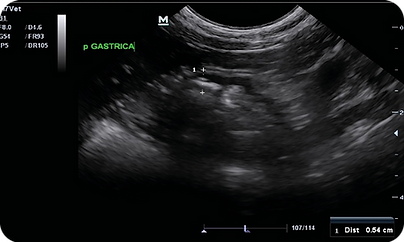

En el ultrasonido abdominal se encotró engrosamiento de la pared gástrica e intestinal (Ver imagen 1 y 2)

Imagen 1. Vista transversal, pared gástrica engrosada (1 cm), el grosor normal en gatos debe ser de 2-4mm.